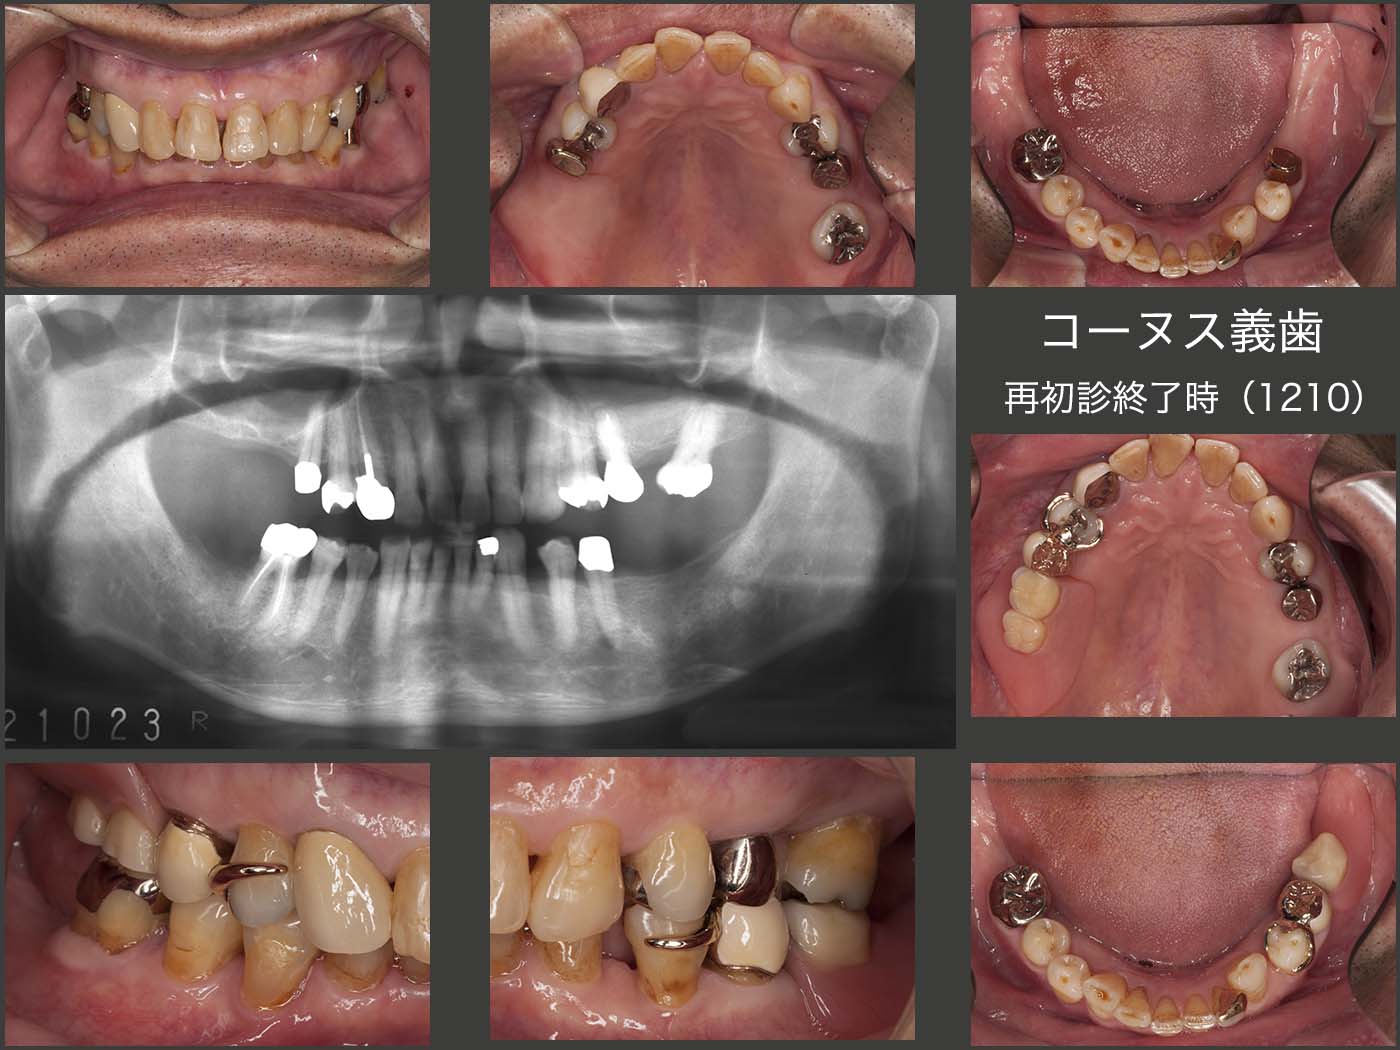

そこで左右側大臼歯部でも咀嚼できるように,コーヌス義歯を製作することにした.通常,遊離端義歯を片側処理するには,歯の欠損部位より前方に2本の支台歯(犬歯まで)が必要である.欠損側に近い直接支台歯(床隣接歯)が義歯に加わる垂直的・水平的負担を担うが,手前の歯は,直接支台歯の水平的負担を軽減するために必要であると考えている.この場合,支台装置はコーヌス冠でなく,クラスプでも構わない.クラスプは審美的には良くないが,歯を削去しないですむという利点がある.また,費用も安価である.

2019年2月,奥様を亡くされたことによる喪失感からかブラッシングに対する意欲が低下してしまった.家はゴミ屋敷の状態で,左下のコーヌス義歯は家のどこかにあるとのこと.暫く様子をみたが,捜す気もなさそうなので,左下5の内冠の上にクラウンを装着(仮着)した.

20年11月,前歯で硬いものを嚙んで,右上1および左上2が同時に歯冠破折した.通常なら保存可能であるが,今回は抜歯し,同部の人工歯および左上5のクラスプを右上のコーヌス義歯とレジン床にて繋ぎ合わせた.ブラッシングは昨年ほどではないが,決してよいとは言えない.